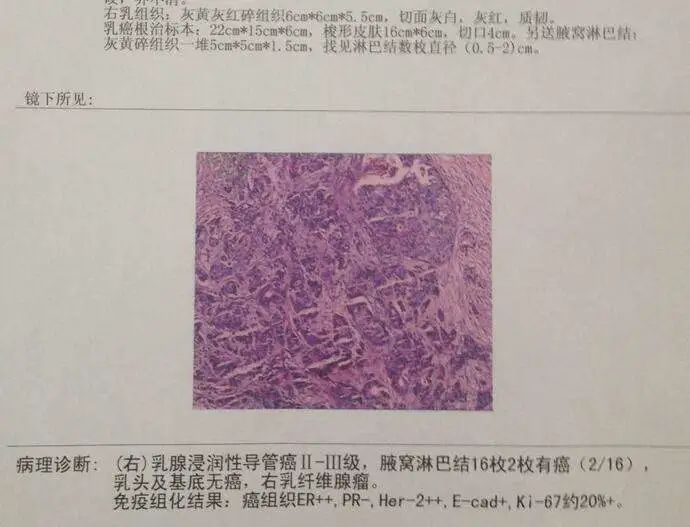

54岁的邓女士10余年前发现左乳肿物,伴有疼痛及乳头溢液,当时未予重视。9个月前在广州某医院就诊,经活检确诊为乳腺浸润性癌,三阴型。影像学检查提示肿瘤巨大、血供丰富,边界不清,肿瘤累及同侧胸壁并伴有多处淋巴结转移及双肺转移。